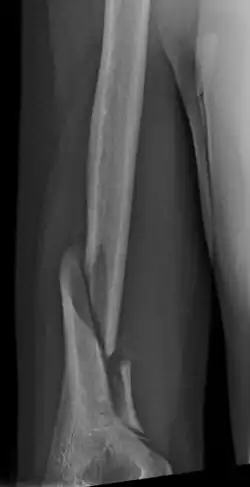

| Holstein–Lewis fracture at 5 weeks post fracture | |

A Holstein–Lewis fracture is a fracture of the distal third of the humerus resulting in entrapment of the radial nerve.